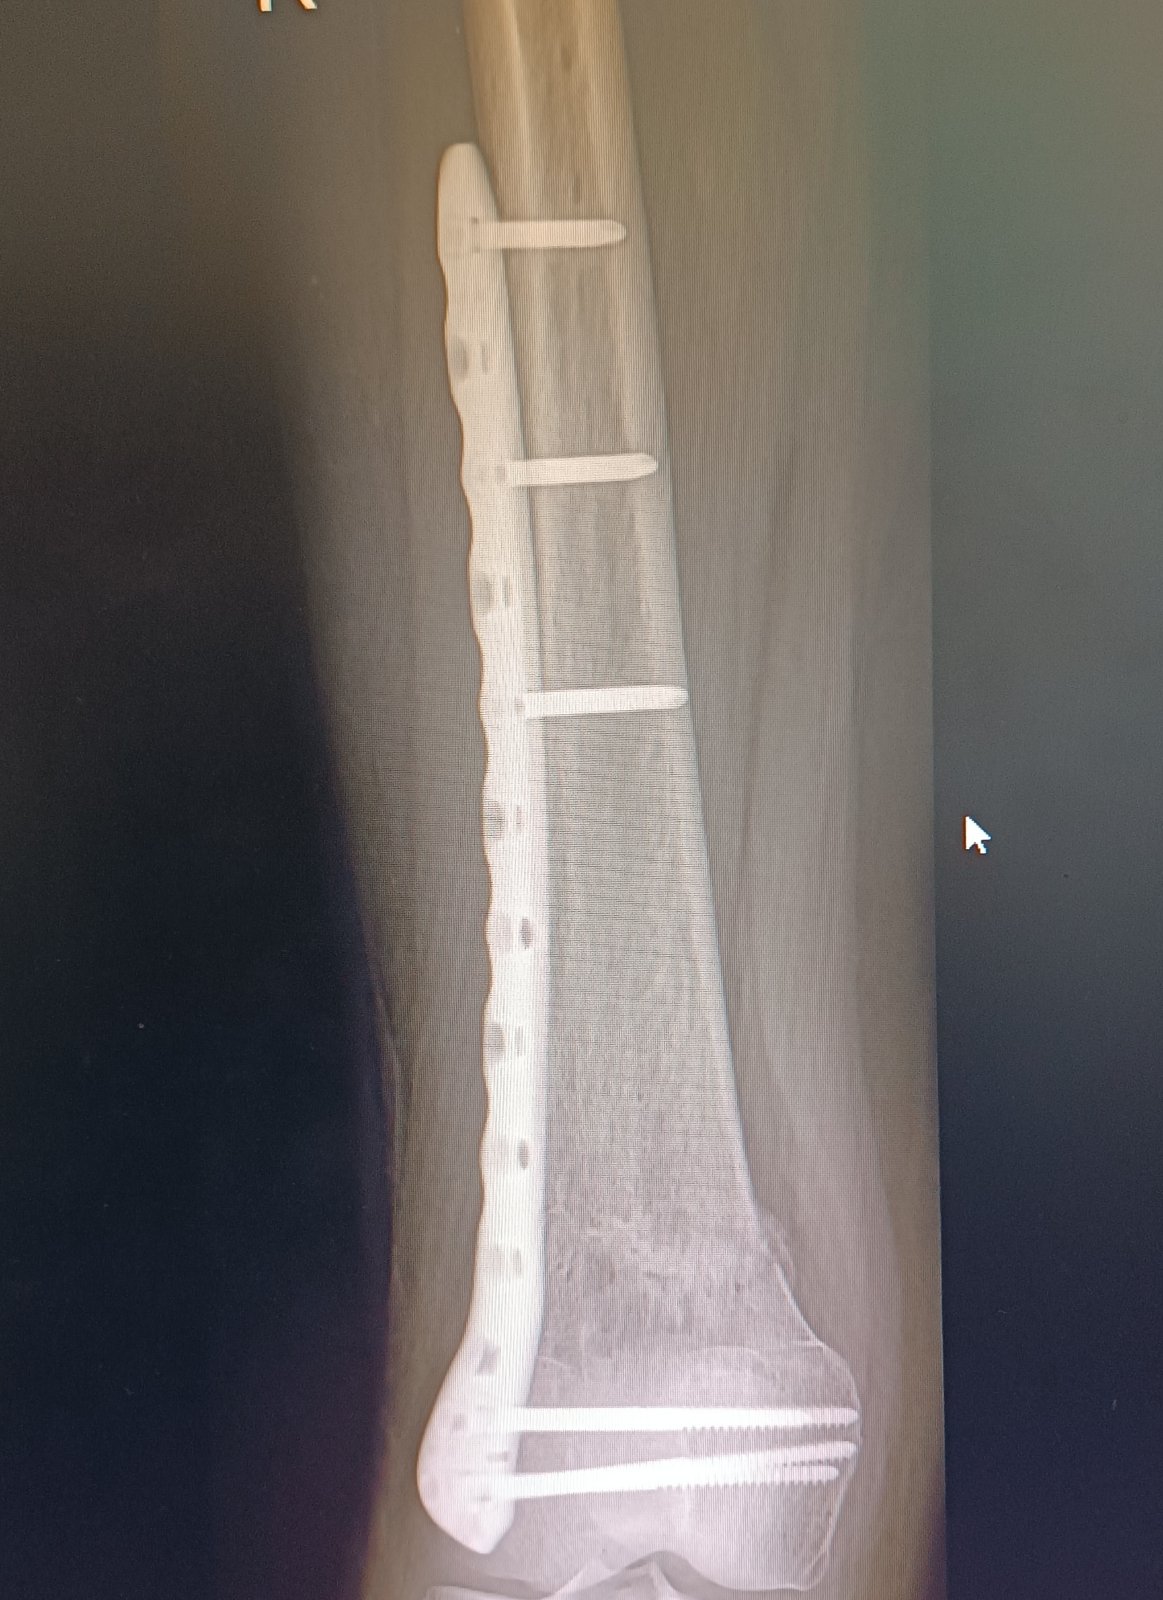

@minenkaa aj mne dávajú na výber jeden doktor bol zato vybrať kvôli veku a tomu že pri dlhšej chodzi mi začne platnička tlačiť na koleno a boli ma skôr sa mi zdalo že v zime to bolo viac ..dnes som bola už teda dohodnúť operaciu a tam iny doktor že by to tam možno aj nechal že na mojom mieste že zas mi to narežu v mieste jazvy a narušia tkaniva a niekedy sa to ani nejak nezlepší že keď tam už bolo zranenie neviem sama čo robiť som s toho na nervy 🙁bojim sa operácie hrozne ale aj toho že mi tam ta platnička bude vadiť keď nastupim do prace ešte som na materskej

@anonym_a80ec7 ano po prvej operácii som si vravela že nikdy viacej že to tam necham navždy ale teraz ..vaham lebo ma boli koleno z toho keď dlho chodim ta platnička tlačí naň preto zvažujem vybratie viem že to tam môže byť navždy len sa bojim aby mi to neskôr nerobilo vetšie problemy .

@dagmara17 neviem ako sa hoja kostí v 34 povedali mi že to mam zahojene čo je spravny vek na vybratie,? Nevybratie? Neviem čo robiť 😔